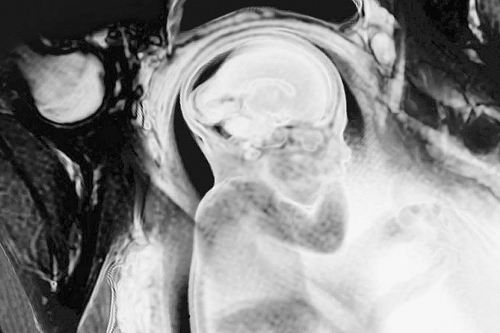

精神分裂症出生前就已经开始了吗? 图片来源:Thierry Berrod, Mona Lisa Production

患有精神分裂症的人在出生时大脑结构可能存在差异。这一发现进一步表明,遗传在精神分裂中扮演着关键角色。

精神分裂症患者的症状倾向于在青少年时期或20岁左右出现,这可能是因为大脑在青春期发育成熟时,神经元修建的常规过程发生错误引起的。研究人员推测,这可能是从子宫中的问题开始的,然后在儿童期一直悄然潜伏在体内。

这项新发现表明,至少对于一些人来说,基因变化会减少miR-9的水平,从而引发神经元迁移或发育问题。“甚至在孩子出生前,基因已经在发挥作用了。”Brennand说。